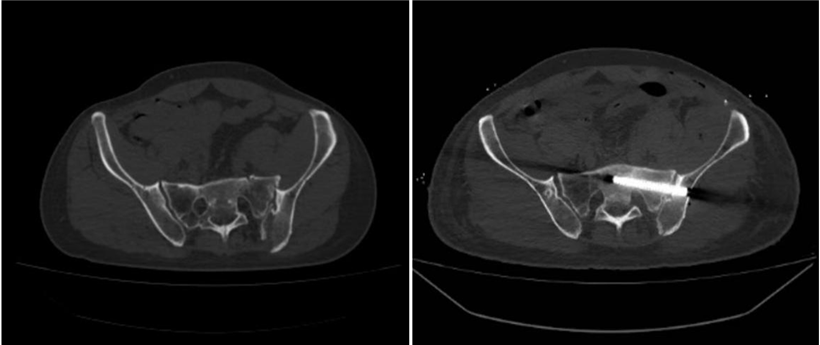

术前影像(左图)及术后影像(右图)对比显示,该患者的骨盆完全复位。